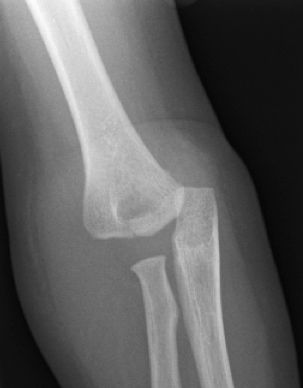

Figura 8: a-d, Imagen radiografica de fractura del cóndilo lateral con desplazamiento articular. Tratamiento quirúrgico mediante reducción abierta y osteosíntesis.